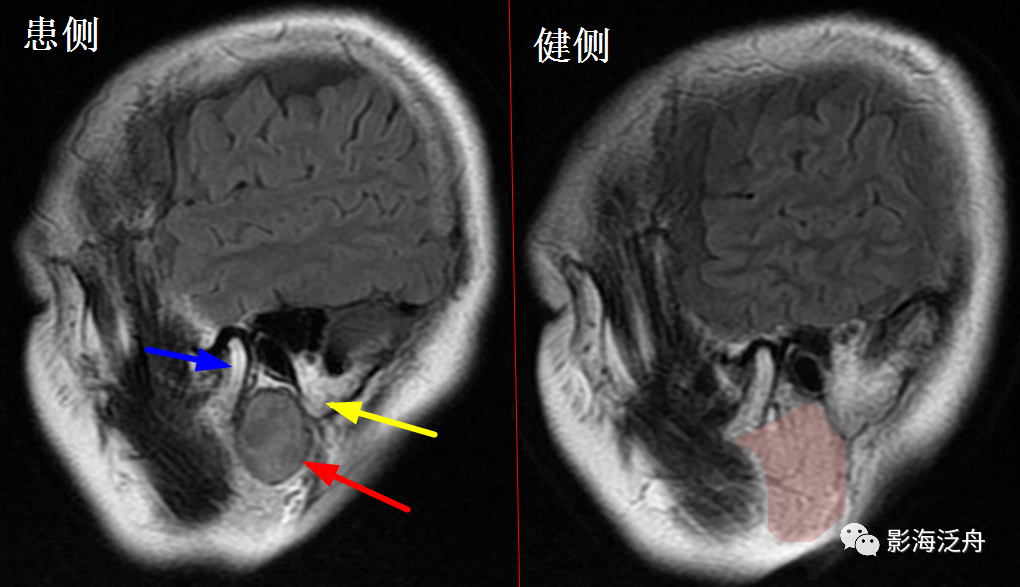

左侧岩尖部囊性病变(红箭头),患者未术,病理不明。MR对骨质结构显示不佳,因此很多读者会忽略掉颅内骨质病变的观察,很多颅内病变,如三叉神经鞘瘤、鼻咽癌等都会造成颞骨岩部(红色标注区)骨质破坏,因此,平时应对此处多加留意。黄箭头指听神经及内耳结构。